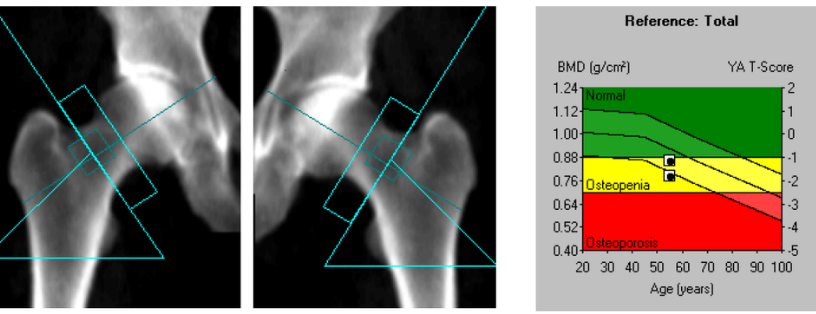

Денситометр Prodigy Primo

- GE Healthcare (США)